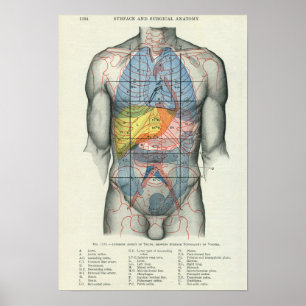

Human Yta Anatomy Relation till organ Poster

Pris258,00 kr

Human Yta Anatomy Relation till organ Poster

Pris258,00 kr